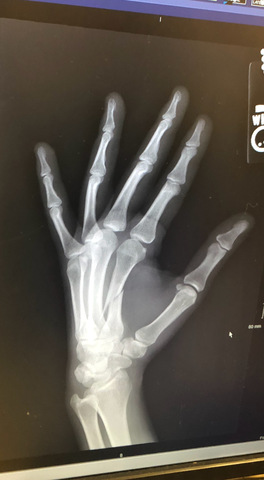

• Injury During Brazilian Jiu Jitsu Training

On June 14th 2018 during a training session live roll/sparring, Lixy's index finger metacarpal bone broke. Lixy was unable to train to the fullest extent for 12 weeks. During that time training was done very carefully in a small 7 by 15 squarefoot area; never live rolling but rather working on perfecting technique carefully. https://www.verywellhealth.com/metacarpal-fracture-a-broken-hand-2549405